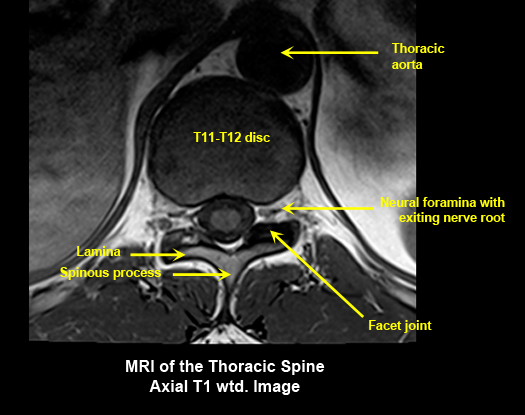

MR Brain and Spine